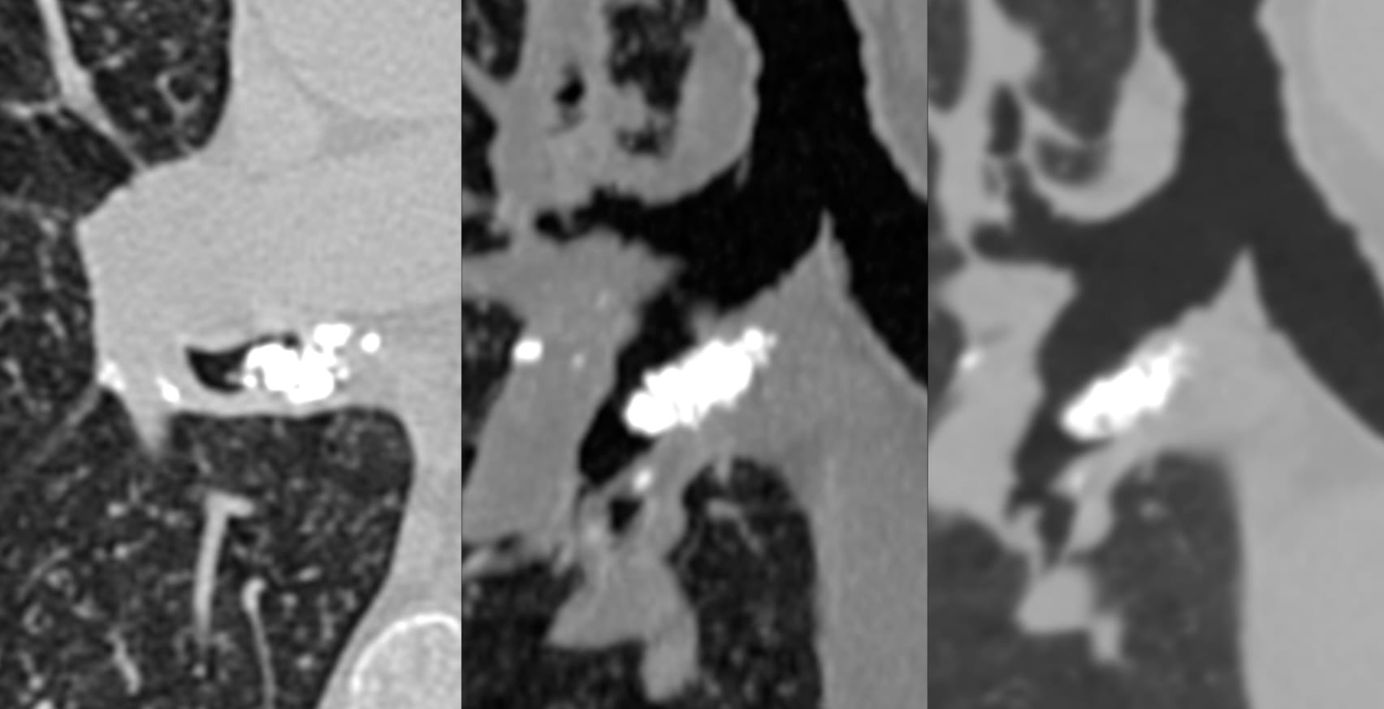

Broncholith

Case of the Day 187 - Stone in the Bronchus

All about broncholiths